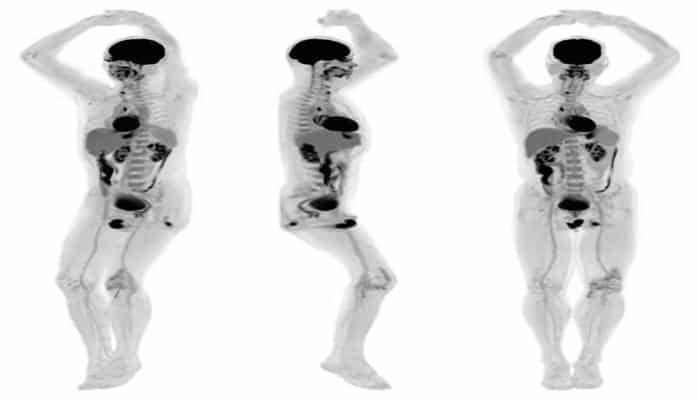

Explorer, первый в мире медицинский сканер, разработан в Калифорнийском университете Дэйвиса. Устройство, способное выдавать трехмерную картину всего человеческого тела, продемонстрировало первые созданные им сканы.

Explorer — это совмещенный аппарат позитронно-эмиссионной томографии и рентгеновской вычислительной томографии, который может сделать снимок всего тела одновременно. Такая машина улавливает радиацию эффективнее других сканеров, продуцирует изображение, а затем создает целые фильмы, на которых можно увидеть, как специально помеченные лекарства передвигаются по всему телу. Разработчики полагают, что у новой технологии будет множество областей применения: от улучшенной диагностики до отслеживания развития болезней и новых лекарственных терапий.

Ожидается, что Explorer будет производить диагностический скан всего тела за 20−30 секунд. Доза радиации при таком сканировании в 40 раз меньше, чем при обычной томографии, что открывает новые пути для исследования. Например, теперь можно проводить множество повторных исследований на одном человеке или наоборот радикально снизить дозу при педиатрических исследованиях.

Впервые в истории медицины томограф сможет оценить, что происходит во всех органах и тканях тела одновременно. Например, он может комплексно измерить уровень кровотока или посмотреть, как тело вбирает глюкозу по всему телу. Исследователи уже говорят о том, что на таком приборе можно будет увидеть, не распространяется ли рак за пределами одной опухоли. Это же касается распространения инфекций, воспалений, иммунологических или метаболических заболеваний.